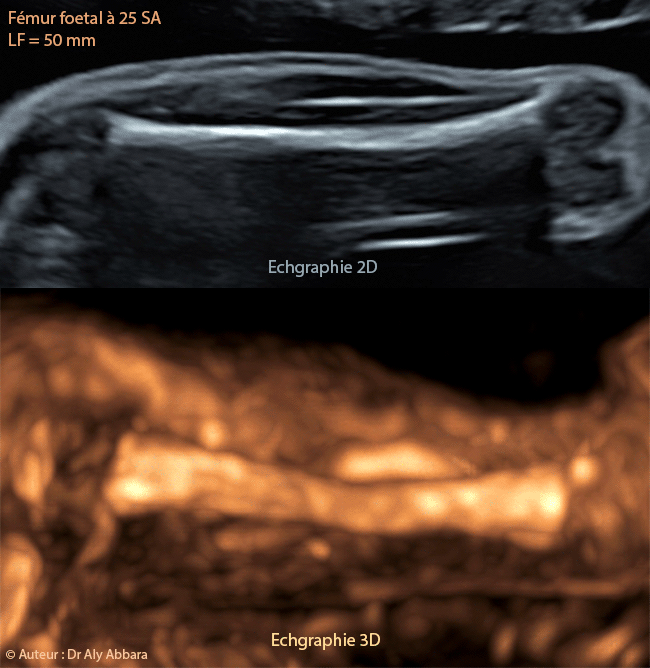

Fémur foetal à 25 SA (50 mm de longueur) - Aspect en échographie 2D et 3D

Fémur fœtal à 25 SA (Longueur fémorale = 50 mm).

Images fœtales comparant l'aspect du fémur en échographie 2D et en échographie 3D à 25 SA.

La partie identifiable du fémur à ce terme de grossesse est seulement la diaphyse.